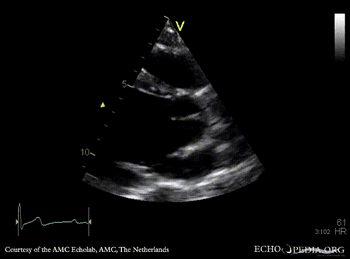

E00231.gif E00232.gif

PLAX: prolapse of aortic valve PLAX: Color Doppler severe aortic regurgitation, eccentric jet